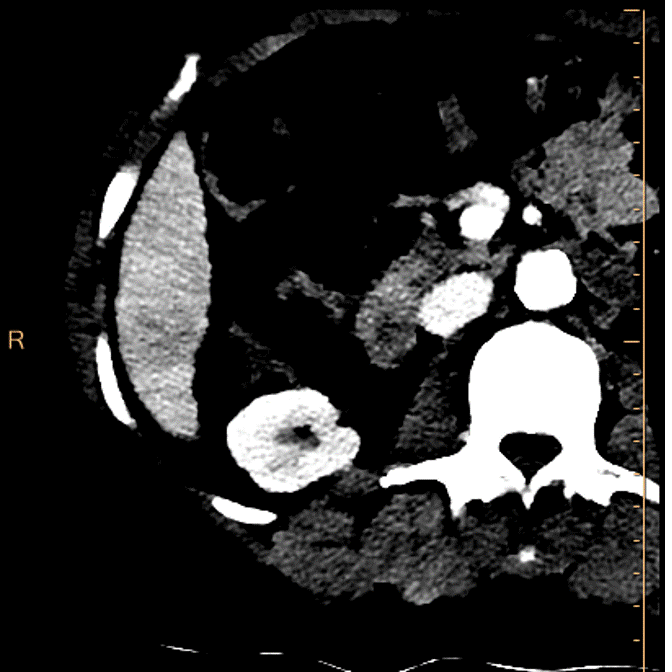

72 year old male, with chronic hepatitis C, genotype 6 (could not complete treatment), presents with weight loss. Past history of HCC with chemoebolization. AFP is normal. A CT scan with liver protocol is ordered. Turns out he also has chronic renal failure with eGFR in the 30’s. BMI is 21.

Patient is in the department for the scan. We decide to use Spectral CT to reduce dose of contrast. After a true non-contrast scan (done as he had previous chemoembo), the multiphasic scan is done with 35 mL of omnipaque 350.

On images below, it is obvious Spectral CT helps in many ways. On the non-contrast phase, the 2.4 cm lesion in segment 6 is so much more obvious on the electron-density image (you know I like EDW). On the arterial phase and delayed phase, the lesion shows enhancement and washout respectively, and both are so much better seen on the 40 keV monoenergy reconstruction. This is a liRADS 5 lesion(definite HCC).

Non-contrast CT. Can you see the lesion?

Electron density: Can anyone miss the lesion?